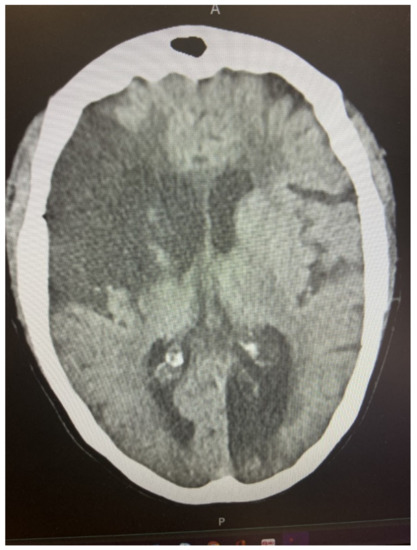

| 4 | Seizure associated with the onset of the acute neurological deficit; |

| 5 | Multiple cerebral vascular territory involvement; |

| 1 | Cardioembolic stroke |

| 2 | Cerebral hemorrhage as a complication of anticoagulant therapy |

| 3 | Cerebral hypoperfusion |